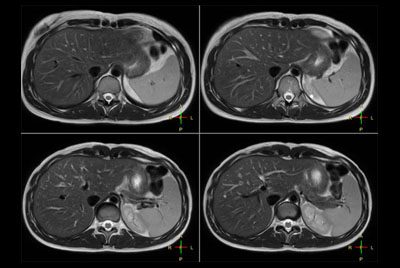

SmartSpeed Liver